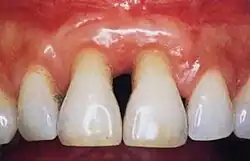

Normal gingiva may range in color from light coral pink to heavily pigmented. The soft tissues and connective fibres that cover and protect the underlying cementum, periodontal ligament and alveolar bone are known as the gingivae. The gingivae are categorized into three anatomical groups: the free, attached and the interdental gingiva. Each of the gingival groups are considered biologically different; however, they are all specifically designed to help protect against mechanical and bacterial destruction.[3]

Healthy gingiva can be described as stippled, pale or coral pink in Caucasian people, with various degrees of pigmentation in other races.[15] The gingival margin is located at the cemento-enamel junction without the presence of pathology. The gingival pocket between the tooth and the gingival should be no deeper than 1–3mm to be considered healthy. There is also the absence of bleeding on gentle probing.[11]